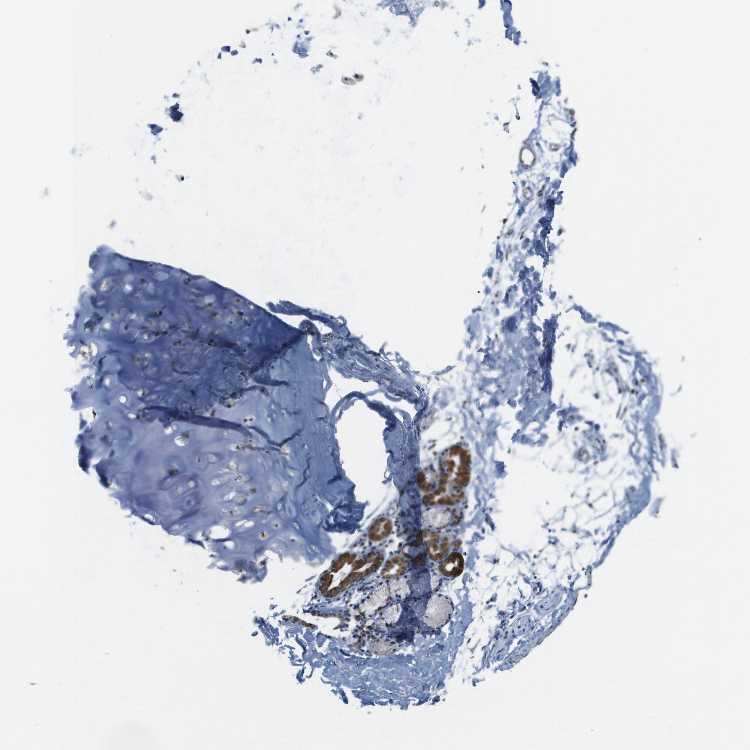

SOFT TISSUE 1 - Antibody stainingi

Antibody staining in the annotated cell types in the current human tissue is reported as not detected, low, medium, or high, based on conventional immunohistochemistry profiling in selected tissues. This score is based on the combination of the staining intensity and fraction of stained cells.

Each image is clickable and will lead to virtual microscopy that enables deeper exploration of all samples and also displays staining intensity scores, fraction scores and subcellular localization as well as patient and tissue information for each sample.

Antibody HPA017160

Chondrocytes Medium

Fibroblasts Medium

Peripheral nerve Not detected

SOFT TISSUE 2 - Antibody stainingi

Peripheral nerve Low